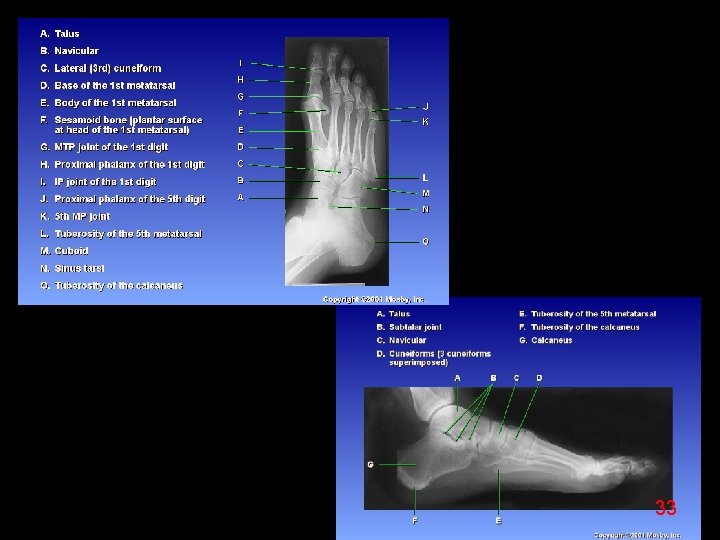

32

33